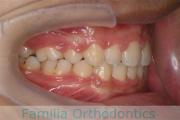

No.14V-516

- 主な症状:

- 上顎前突

- その他の症状:

- 叢生

- 年齢:

- 10歳

- 性別:

- 女性

- 抜歯部位

- 上:

- 44

- 下:

- 55

- 主な使用装置:

- FEA

- 治療にかかった費用:

- 90万円

きれいな歯並びにしたいということで来院されました。第一期治療で六歳臼歯の位置を維持する装置を入れて第二期治療の準備をしました。第二期は中学生になってから小臼歯を抜歯して行いました。二期治療は約2年半、25回程度の通院が必要でした。

二期治療開始前は叢生(でこぼこ、凹凸、ガタガタ)がかなりありましたので、保定をしっかりしないと段差ができてきたり後戻りのリスクがあります。